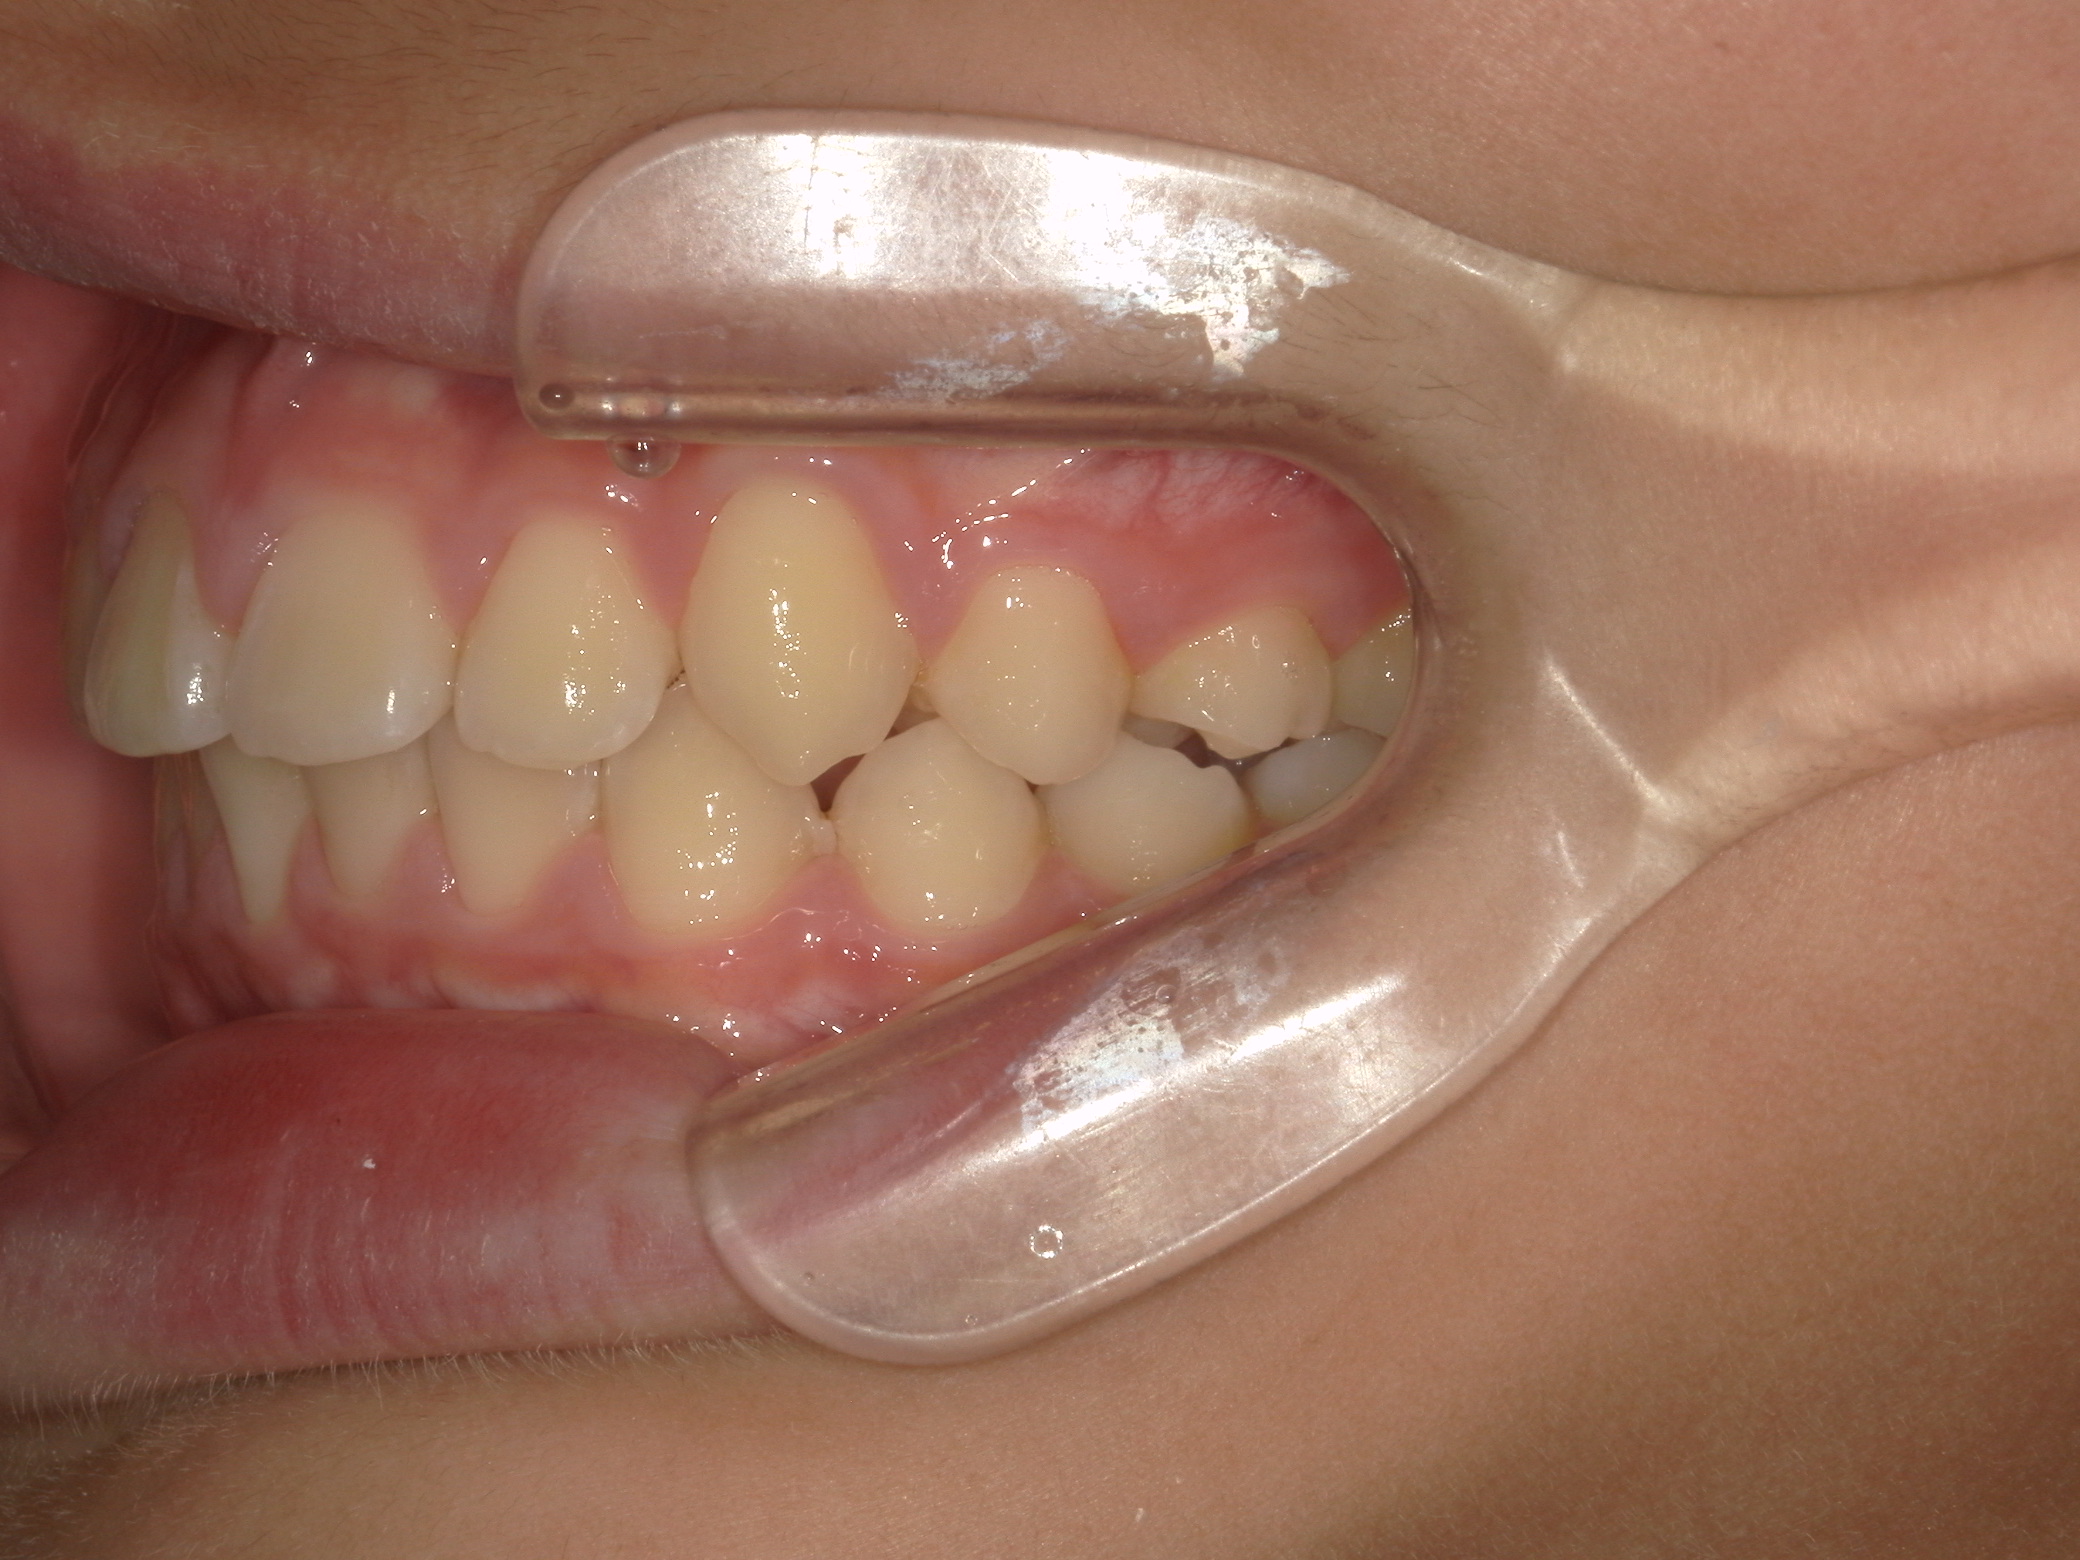

【小学生】 8歳 インビザライン矯正 過蓋咬合(深い咬み合わせ)と叢生(でこぼこ)を改善

小学生で開始

インビザライン ファースト

でこぼこ

非抜歯

1期治療のみで改善

Before

After

治療期間

1年4カ月年

治療開始

8歳

種類

インビザライン矯正

使用装置

インビザラインファースト(こどものインビザライン)

コメント

転勤族ということもあり、時間に制限がありましたが、患者さんがしっかり装置をつけてくれたので お引越しまでに終了することができました。

途中 側方の歯がどんどん生え変わって 最終的には全部永久歯で終了しました。

咬み合わせが深い場合、インビザラインファーストは咬み合わせを浅くするのに適しています。